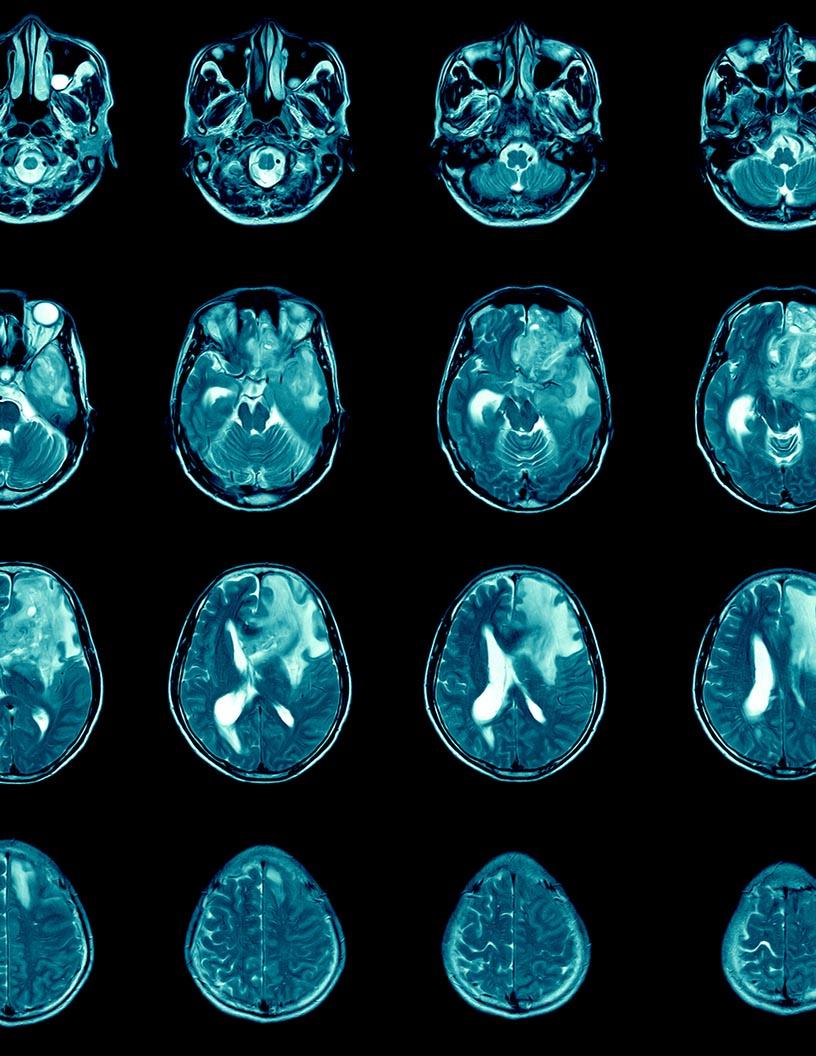

The Glioblastoma Multiforme Treatment Market is expected to grow at a CAGR of 8.2% during 2023 and 2028. During this period, the market is also expected to show a growth of USD 1362 million. The glioblastoma multiforme (GBM) treatment market is witnessing significant growth due to the escalating research and development activities. The urgent requirement for more effective therapies, given the limited success of traditional treatments, is driving this trend. Innovative approaches, such as DCVax-L, a personalized cancer vaccine utilizing dendritic cells to stimulate an immune response against GBM, have demonstrated promising results in phase III clinical trials for extending survival in patients with newly diagnosed or recurrent GBM. Furthermore, novel strategies like Tumor Treating Fields (TTF), which employ alternating electric fields to disrupt tumor cell division, are gaining traction as non-invasive treatment options. These advancements underscore the market's potential for substantial growth.

The Glioblastoma Multiforme (GBM) treatment market is witnessing significant advancements with various innovative therapies. These include focused ultrasound, proton beam therapy, car T-cell therapy, oncolytic viruses, and nanoparticle drug carriers. Research is ongoing into immune checkpoint inhibitors, signal transduction pathways, miRNA expression, methylation markers, tumor infiltrating lymphocytes, PD-L1 expression, tumor vascularity, receptor tyrosine kinases, and drug metabolism enzymes. Cell signaling pathways, cell death pathways, DNA damage response, brain metastases, tumor recurrence, radiomics analysis, treatment efficacy, and survival benefit are also being explored. Neurocognitive function, patient selection criteria, treatment sequencing, complementary therapies, symptom management, palliative care, clinical outcome measures, adverse events, treatment toxicity, performance status, functional MRI, and diffusion tensor imaging are essential considerations in GBM treatment.

The Glioblastoma Multiforme (GBM) Treatment Market is a significant segment of the global pharmaceuticals industry, encompassing entities involved in the research and development (R&D) or production of various types of drugs, including generics, non-generics, and veterinary drugs. Key growth drivers for this market include advancements in tumor microenvironment understanding, innovative therapies such as oncolytic virotherapy and targeted drug delivery, and the potential for enhanced immunotherapy responses. Technavio projects the global pharmaceuticals market size, which includes the revenue generated by manufacturers and providers of equipment, supplies, pharmaceuticals, biotechnology, and life sciences tools and services, will be propelled by demographic shifts, with the aging population in the US and Europe projected to reach nearly one-quarter by 2050 and 2030, respectively. This demographic trend, coupled with the increasing prevalence of cancer and neurological disorders, will create significant demand for advanced GBM treatments. Radiation therapy and chemotherapy remain common treatment modalities, but chemotherapy resistance poses a significant challenge, necessitating the development of novel therapeutic approaches.. Industries are leveraging the products belonging to the market for customer engagement, transactional notifications, and promotional offers.